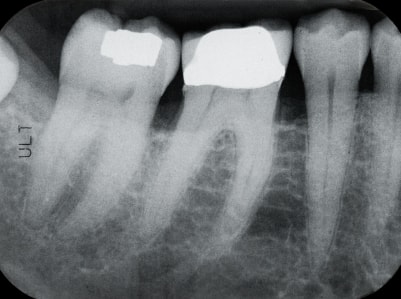

One of the major causes of inflammation are teeth and gums. Some of the reason may be poor dental work or poor hygiene. When the pouches of infection and inflammation form in the gums and poor dental hygiene is added, it can be a killer concoction. Diet becomes another factor, where too many sweets and carbohydrates help bacteria build up.

You can work on getting inflammation down by taking better care of your teeth. Get rid of sweets, firstly. Clean teeth naturally by eating raw vegetables. Using toothpaste is not the best idea, for the simple reason that often there is a number on the box to call poison control if you swallow too much. That means there are poisons in it that yo do not really need. Dental work should be done and not put off. Make sure it is quality dental work. Getting a root canal done, and having a cap put on for example, can cause bacteria to grow and inflammation to blossom. Don?t have wisdom teeth removed unless its really necessary, because there is no same reason for everyone to remove them! When those teeth are removed, it changes the way that we chew and can affect so much the digestion process in our bodies. Bottom line is simple; take care of your teeth and it will pay off!

Do you have a lot of cavities, filled with mercury laden amalgam?

Do you have root canals?